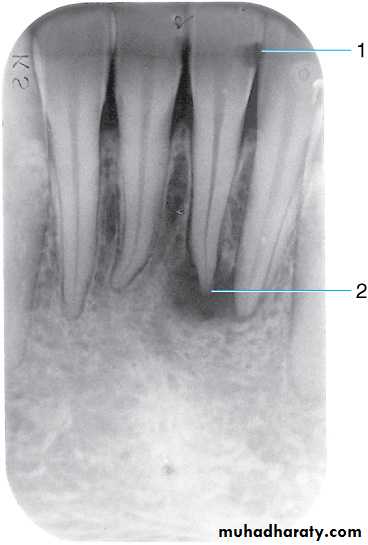

This radiograph shows (1) radiolucent restorations (composites) on the mesial surface of the lateral incisor and distal surface of the central incisor. Note that under both restorations is a base of radiopaque material. (2) The radiolucencies on the mesial surfaces of both central incisors are carious lesions.

Retention pins. (1) Radiopaque pins help retain the radiolucent composite restorations. (2) Small radiopaque amalgam restorations.